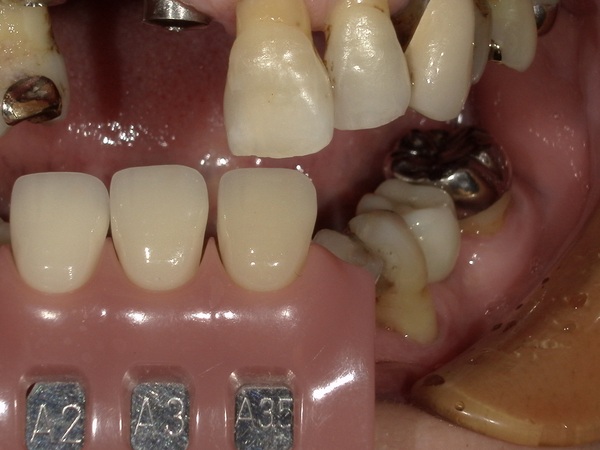

隣の歯と自然な被せ物が入るように色合わせの写真を何枚も撮りました。

こちらが前歯のジルコニアセラミックの写真になります。よく見るとジルコニアにセラミックが足されているのが分かります。

技工士さんが写真を見ながら、歯の根の色や細かい色調を似せて作っていきますので、自然の歯にかなり近い状態で被せ物が再現されております。